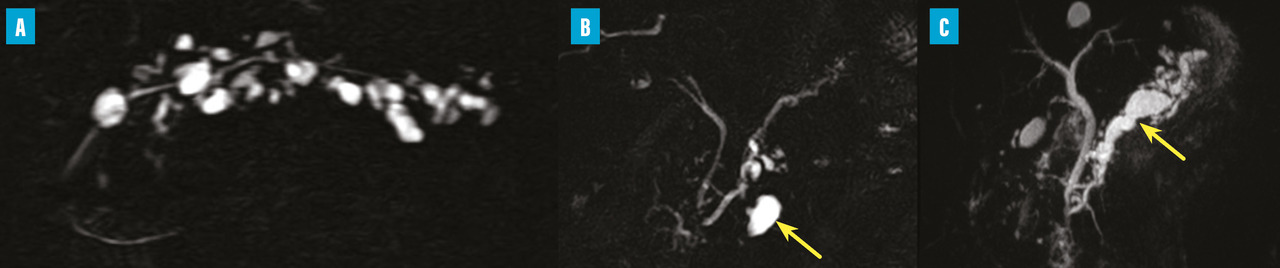

Les TIPMP sont des lésions canalaires intra-épithéliales développées aux dépens des canaux pancréatiques (principal ou/et secondaires) [fig. 1]. Elles prédominent au niveau de la tête et du crochet, mais peuvent concerner toute la glande. La composante kystique des TIPMP présente un épithélium de type mucineux avec production de mucus. Au cours du processus d’oncogenèse, des papilles commencent à se former, et différents phénotypes cellulaires distincts ont été décrits, corrélés à leur pronostic.

Les recommandations pour la prise en charge et le suivi des patients avec TIPMP se sont complexifiées, avec un enchaînement de publications de recommandations  : internationales en 2017,4 européennes en 20185 et par un groupe d’experts en 2024.6

Au vu des données épidémiologiques et de la prévalence des lésions kystiques pancréatiques, la proportion de la population française présentant une TIPMP est vraisemblablement grande. Dans une étude en population générale adulte française,7 la prévalence des TIPMP des canaux secondaires était de 7 %, sachant que ce taux augmente avec l’âge et pourrait être supérieur à 10 % au-delà de 60 ans. Cela représente plusieurs millions de Français porteurs d’une TIPMP des canaux secondaires. Sachant que l’incidence du cancer du pancréas est estimée à 16 000 nouveaux cas par an et que l’on estime qu’environ 10 % des cancers se développent sur une lésion de TIPMP préexistante, on peut affirmer facilement que le risque de malignité des TIPMP est très faible.

Les experts distinguent des critères à haut risque de malignité (indications absolues à une résection chirurgicale) et des signes d’inquiétude (indications relatives à une résection préventive) [tableau]. Selon les données de la littérature, le taux de survie ­spécifique à cinq ans est meilleur dans le groupe de patients avec signes d’inquiétude comparativement au groupe de patients avec critère à haut risque de malignité (96,2 % versus 60,2 %).8

Le schéma de surveillance proposé par les experts européens est présenté dans la figure 2. Cependant, la pertinence médicale de ce schéma de prise en charge n’a pas été évaluée  ; de plus, cette surveillance a un coût dont le potentiel bénéfice médico-économique n’est pas connu à ce jour. Les Européens proposent de suivre ce schéma tant que les patients sont éligibles à une chirurgie.

Dans une étude publiée en 2017, ayant inclus 363 patients suivis plus de cinq ans pour TIPMP des canaux secondaires, le risque de cancer était de 2,4 % au cours des cinq premières années de suivi et de 4,4 % ensuite. Le risque de malignité (lésion de haut grade ou invasive) était respectivement de 4,3 et 5,5 %.9